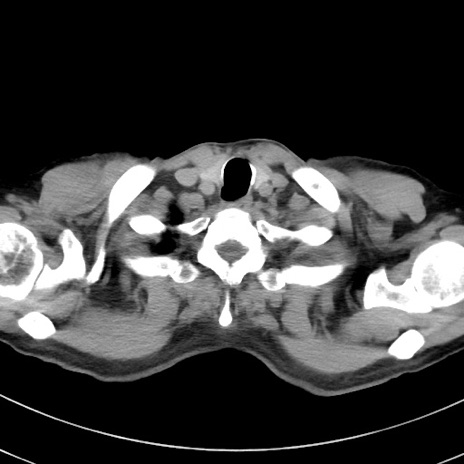

症例38(横断像)

【症例】70歳代 男性

【主訴】腹痛・嘔吐

【現病歴】昨晩より、嘔吐・腹痛あり。今朝になっても嘔吐あり。来院。

【既往歴】心臓バイパス手術、開腹胆摘、腸閉塞

【身体所見】BP 107/71mmHg、HR 116/min、腹部:平坦、軟、下腹部に軽度圧痛あり。反跳痛なし。

【データ】WBC 15100、CRP 0.32